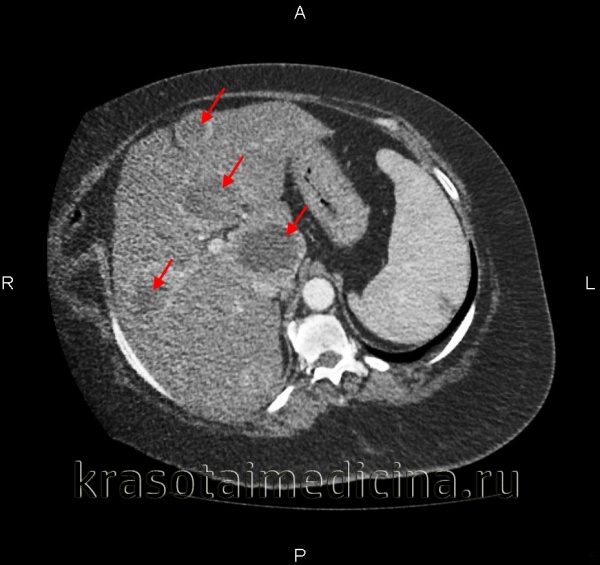

Компьютерная томография (КТ) с контрастированием, магнитно-резонансная томография (МРТ), радиоизотопное сканирование печени, ангиография (контрастное исследование сосудов) применяются для получения дополнительной информации, необходимой при планировании объема операции.

Специфических методов диагностики не существует. Общий осмотр и пальпация живота позволяют определить наличие образования в правом подреберье. УЗИ печени и брюшной полости выявляет расположение опухоли, количество узлов, поражение печеночных сосудов и нижней полой вены. КТ и МРТ, радиоизотопное сканирование печени и ангиография помогают при определении стадии заболевания и планировании объема операции. Рентгенография грудной клетки и брюшной полости позволяют установить метастатическое поражение других органов, наличие в основной опухоли кальцификатов, исключить другие новообразования. Биопсию печени выполняют в случае сомнительного диагноза.

КТ органов брюшной полости. Множественные вторичные опухоли печени (первичная опухоль – рак молочной железы)